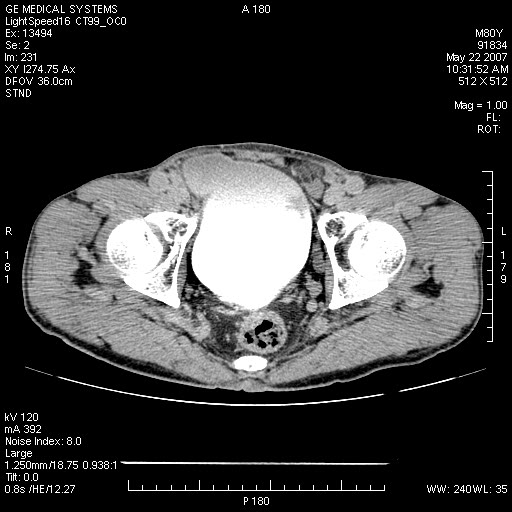

膀胱病变:

增强原原发性肝癌、膀胱癌伴左侧盆腔淋巴转移。

可能为双原发,肝癌,膀胱癌.盆腔淋巴结转移!

肝脏内病灶有假包膜,增强扫描动脉期有动静脉瘘,有快进快出特点,考虑原发性肝癌。病灶内有裂隙样低密度影,以纤维板层样细胞癌可能性大。膀胱左侧乳头状占位,增强呈明显强化,左侧盆腔内有肿大淋巴结,结合有血尿病史,考虑膀胱癌左侧盆腔淋巴结转移。